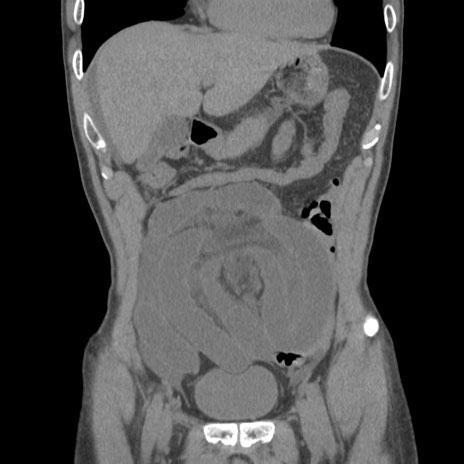

症例56 CT(冠状断像)

横断像